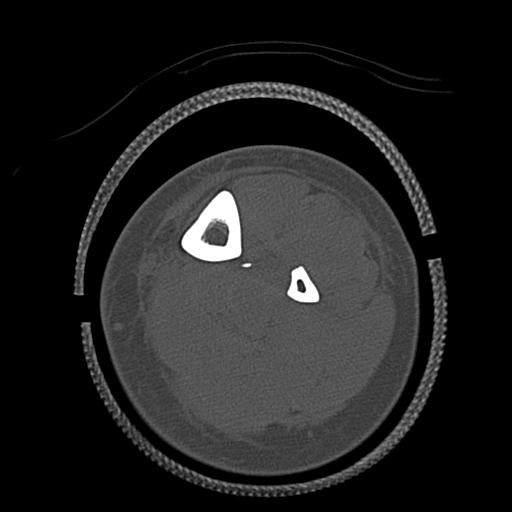

102803 1/12(キウスなし) 1/27 左下腿 4R 30歳女性 左脛骨軸内釘